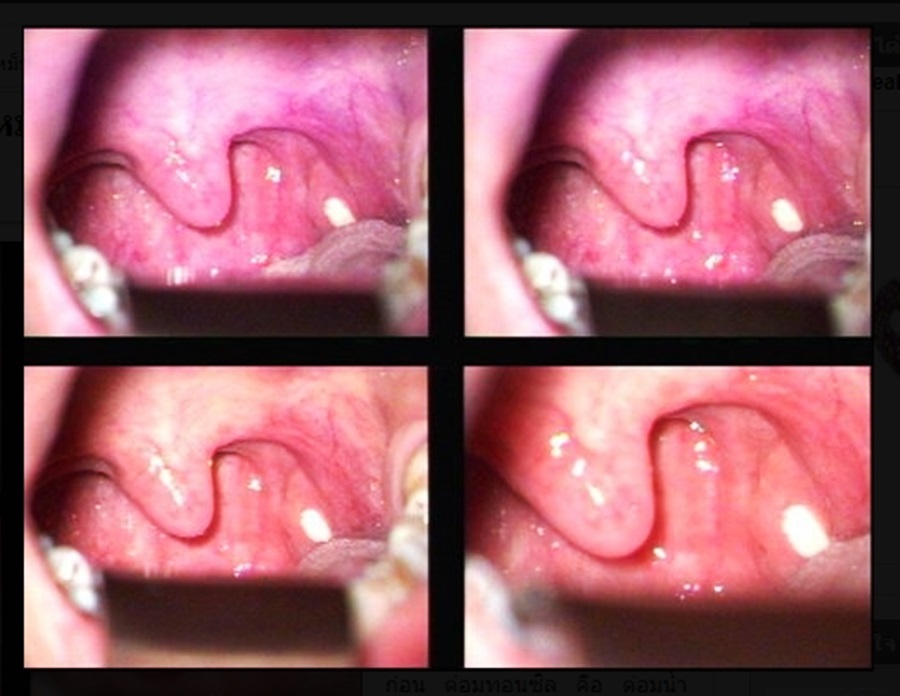

편도결석은 우선 흡입기로 제거하지만 쉽게 재발할 수 있기 때문에 결석의 원인이 되는 편도선을 치료해야 합니다. 이 때 화성이비인후과는 고주파를 이용한 편도 결석 부분 절제 수술을 시행합니다.

편도선의 홈 깊이에 따라 약간의 차이는 있지만 편도선 전체를 제거하는 것보다 더 쉽게 치료와 회복을 할 수 있습니다.